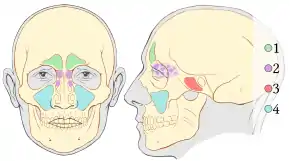

There are two primary types of nasal polyps: ethmoidal and antrochoanal. Ethmoidal polyps arise from the ethmoid sinuses and extend through the middle meatus into the nasal cavity. Antrochoanal polyps usually arise in the maxillary sinus and extend into the nasopharynx and represent only 4–6% of all nasal polyps.[7]

However, antrochoanal polyps are more common in children comprising one-third of all polyps in this population. Ethmoidal polyps are usually smaller and multiple while antrochoanal polyps are usually single and larger.[7]